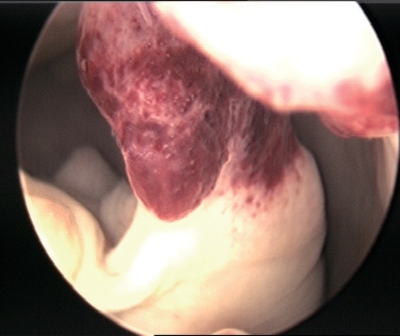

7)子宫内膜癌:病灶局限或扩散、向内或向外生长,可表现为息肉型、结节型、乳头型或溃疡型,表面异形血管爬行,常伴有坏死、感染和出血(图3-17)。